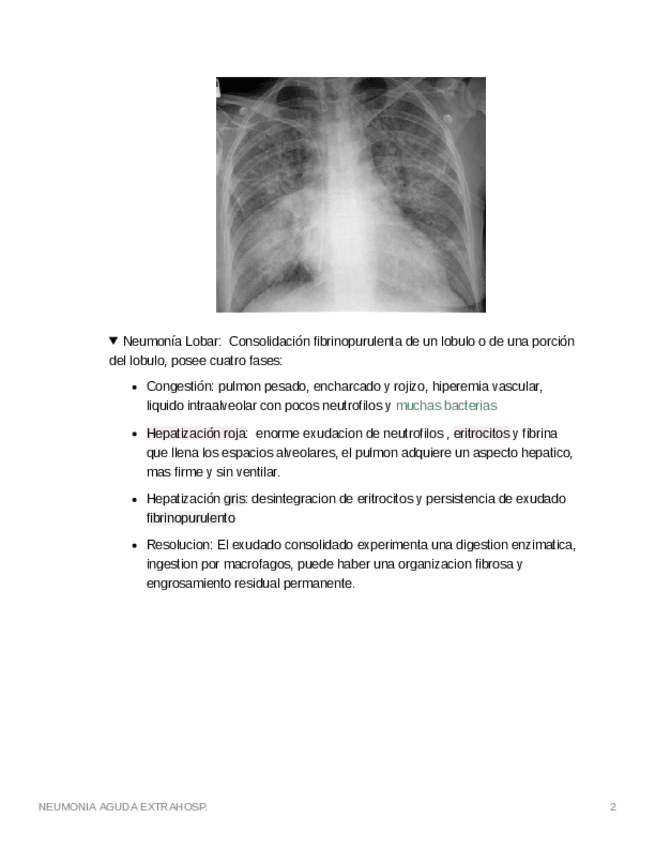

He publicado nuevos apuntes de 2º Prevención de la Enfermedad: Injurias: neumonia-lobar-extrahospitalaria.pdf

4 páginas